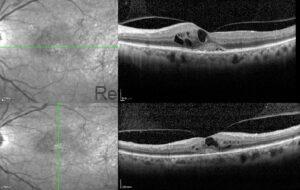

DENS DEPOSIT DISEASE COMPLICATED WITH MACULAR NEOVASCULARIZATION

This was a 30-year-old male who was referred for evaluation of macular degeneration. The patient [...]